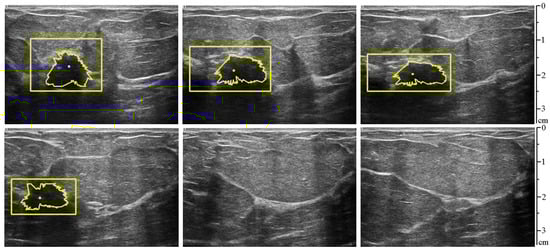

| Video Sequence | Correctly Detected Frames | Incorrectly Detected or Not Detected (Frames) |

|---|---|---|

| First video | 53 out of 60 (88.34%) | 7 out of 60 (11.66%) |

| Second video | 54 out of 60 (90.00%) | 6 out of 60 (10.00%) |

| Total all 52 videos | 2867 out of 3120 (91.89%) | 253 out of 3120 (8.11%) |